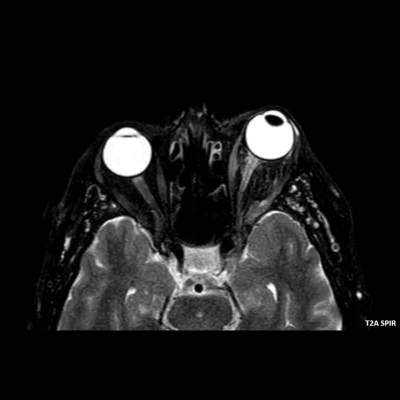

- A) Orbital MRG’de yağ baskılı T2A görüntülerde sol orbital globta ekzoftalmus (ok) izlenmiş olup retrobulbar yağlı dokuda kirlenmeler (ok) ve dilate superior oftalmik ven (ok) dikkati çekiyor. Beyin MRG’de kontrastlı T1A görüntüde sol kavernöz sinüste simetriğine oranla genişleme (ok) izleniyor.

- B) Pre ve post-kontrast yağ basklılı T1A görüntüler incelendiğinde superior oftalmik venin (oklar) kontrast madde verildikten sonra homojen dolum gösterdiği, dilate ve tortiyoze görünümde olduğu izleniyor.

- BT ve MRG: Propitozis, ekstraokuler kaslarda genişleme, superior oftalmik vende genişleme ve tortiyozite, ipsilateral kavernöz sinüste genişleme gösterilebilir. Serebral venöz konjesyonu olan ve intrakraniyal basınçları yükselen hastalarda serebral ödem, hemoraji, leptomeningeal ve kortikal venlerin dilastasyonunu görülebilir. Bunlara ek olarak travmaya sekonder olgularda BT ile eşlik eden fraktürler gösterilebilir.